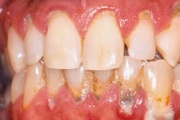

Krooniline parodontiit

Krooniline parodontiit on mikroobide poolt põhjustatud hammaste tugikudede põletik, mille tulemusena tekib progresseeruv alveolaarluu (nähtav röntgenograamil) ja periodontaalligamendi destruktsioon, igemetaskute moodustumine, igeme retsessioon või mõlemad kahjustused kombineeritult. Loe edasi »

- igemed veritsevad (19)

- igemed punetavad (21)

- igemed on tursunud/vohavad (17)

- igemepealne hambakivi (5)

- igemealune hambakivi (4)